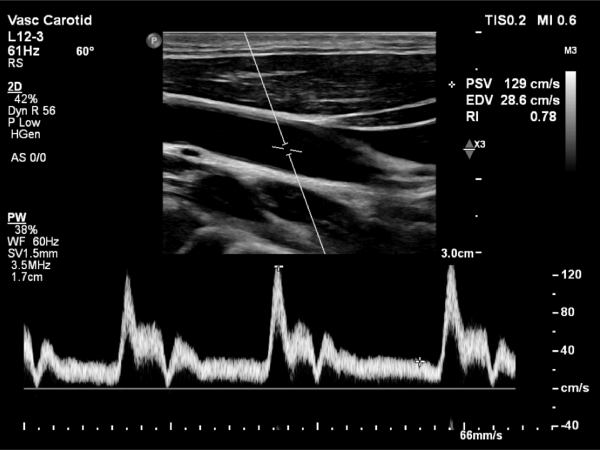

Carotid Artery Ultrasound

Dr. Ghalichi personally performs carotid artery ultrasounds using the state-of-the-art Philips EPIQ Elite (Netherlands) system equipped with AI tools.

• Operator-Dependent Expertise: Benefit from Dr. Ghalichi's specialized skills in conducting and interpreting the ultrasound.

• Intima-Media Thickness (IMT) Measurement: Accurate assessment of the thickness of your arterial walls.

• Radiation-Free Imaging: Safe and painless procedure with no exposure to radiation.

• Trackable Results: Monitor changes in IMT over time to evaluate the effectiveness of treatment strategies.

Carotid Artery Image